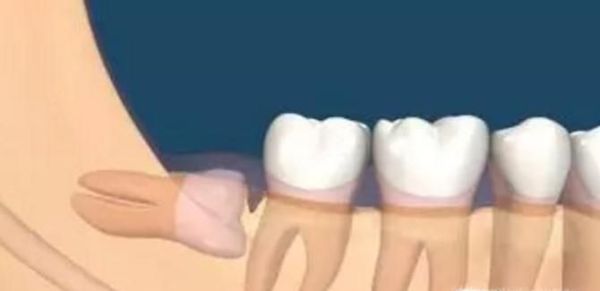

04、最后,我们需要根据实际情况来确定是否需要拔掉智齿,如果智齿直接顶到另一颗牙齿生长的话,这样的智齿我们也是需要拔除的,不然我们的整体牙齿都会有一定的伤害,这是必须要拔的。